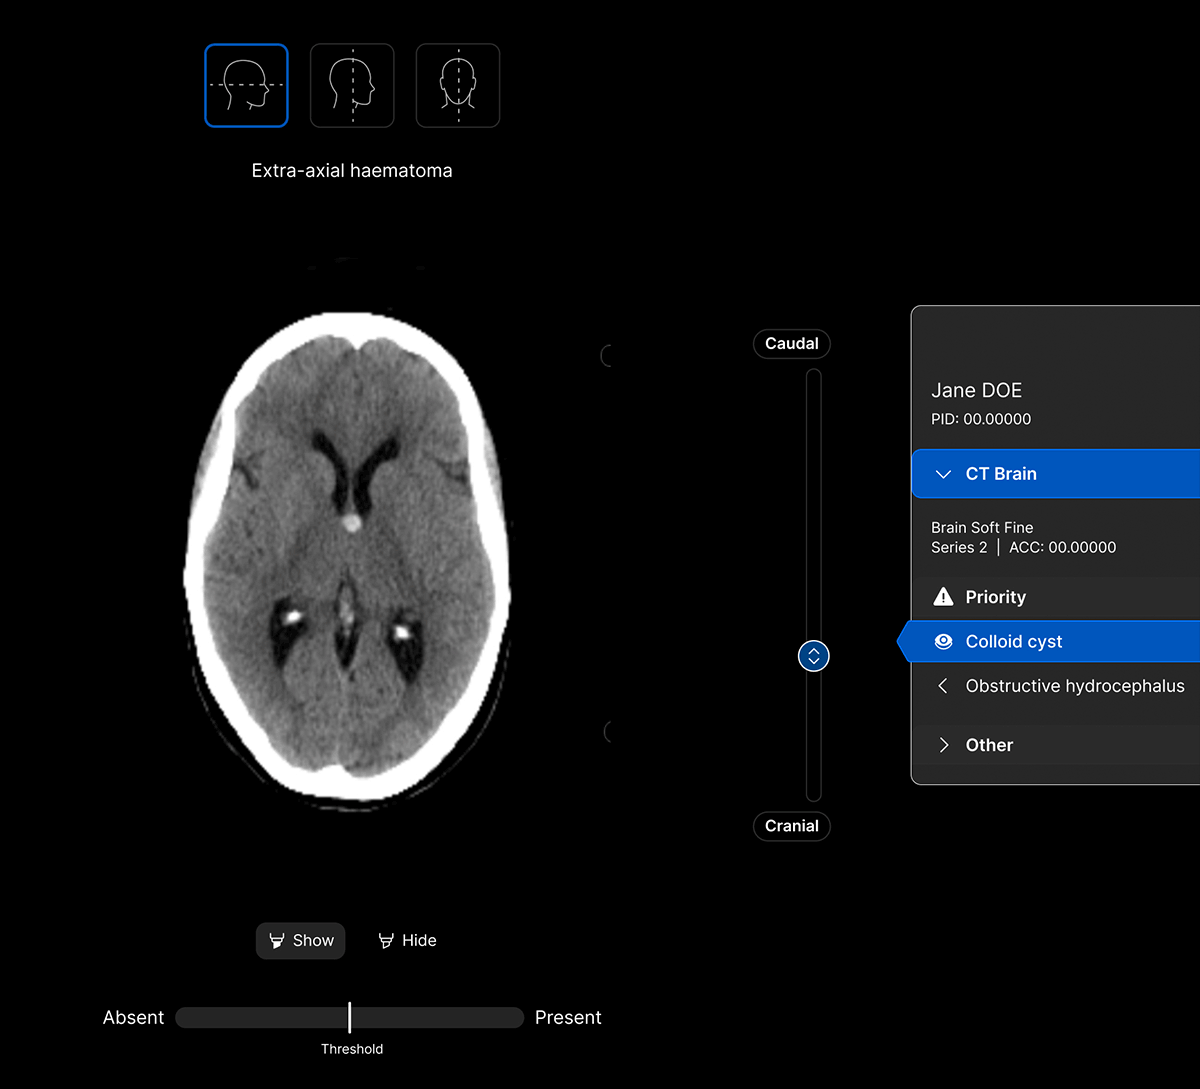

The UI integrates seamlessly with PACS/ RIS, displaying a resizable, no-click overlay window with findings and localisation.

Intelligent worklist prioritisation.

Optimise care pathways with AI-powered Worklist Prioritisation.

- Cases are automatically analysed as soon as they’re acquired and AI results are available within 90 seconds.

- Flag patients with urgent findings.

- Configurable study priority groups for customised workflows.

Maximise clinical value and simplify your workflow with a single comprehensive solution for non-contrast head CT studies, identifying up to 130 findings. No need to juggle multiple solutions for different findings.